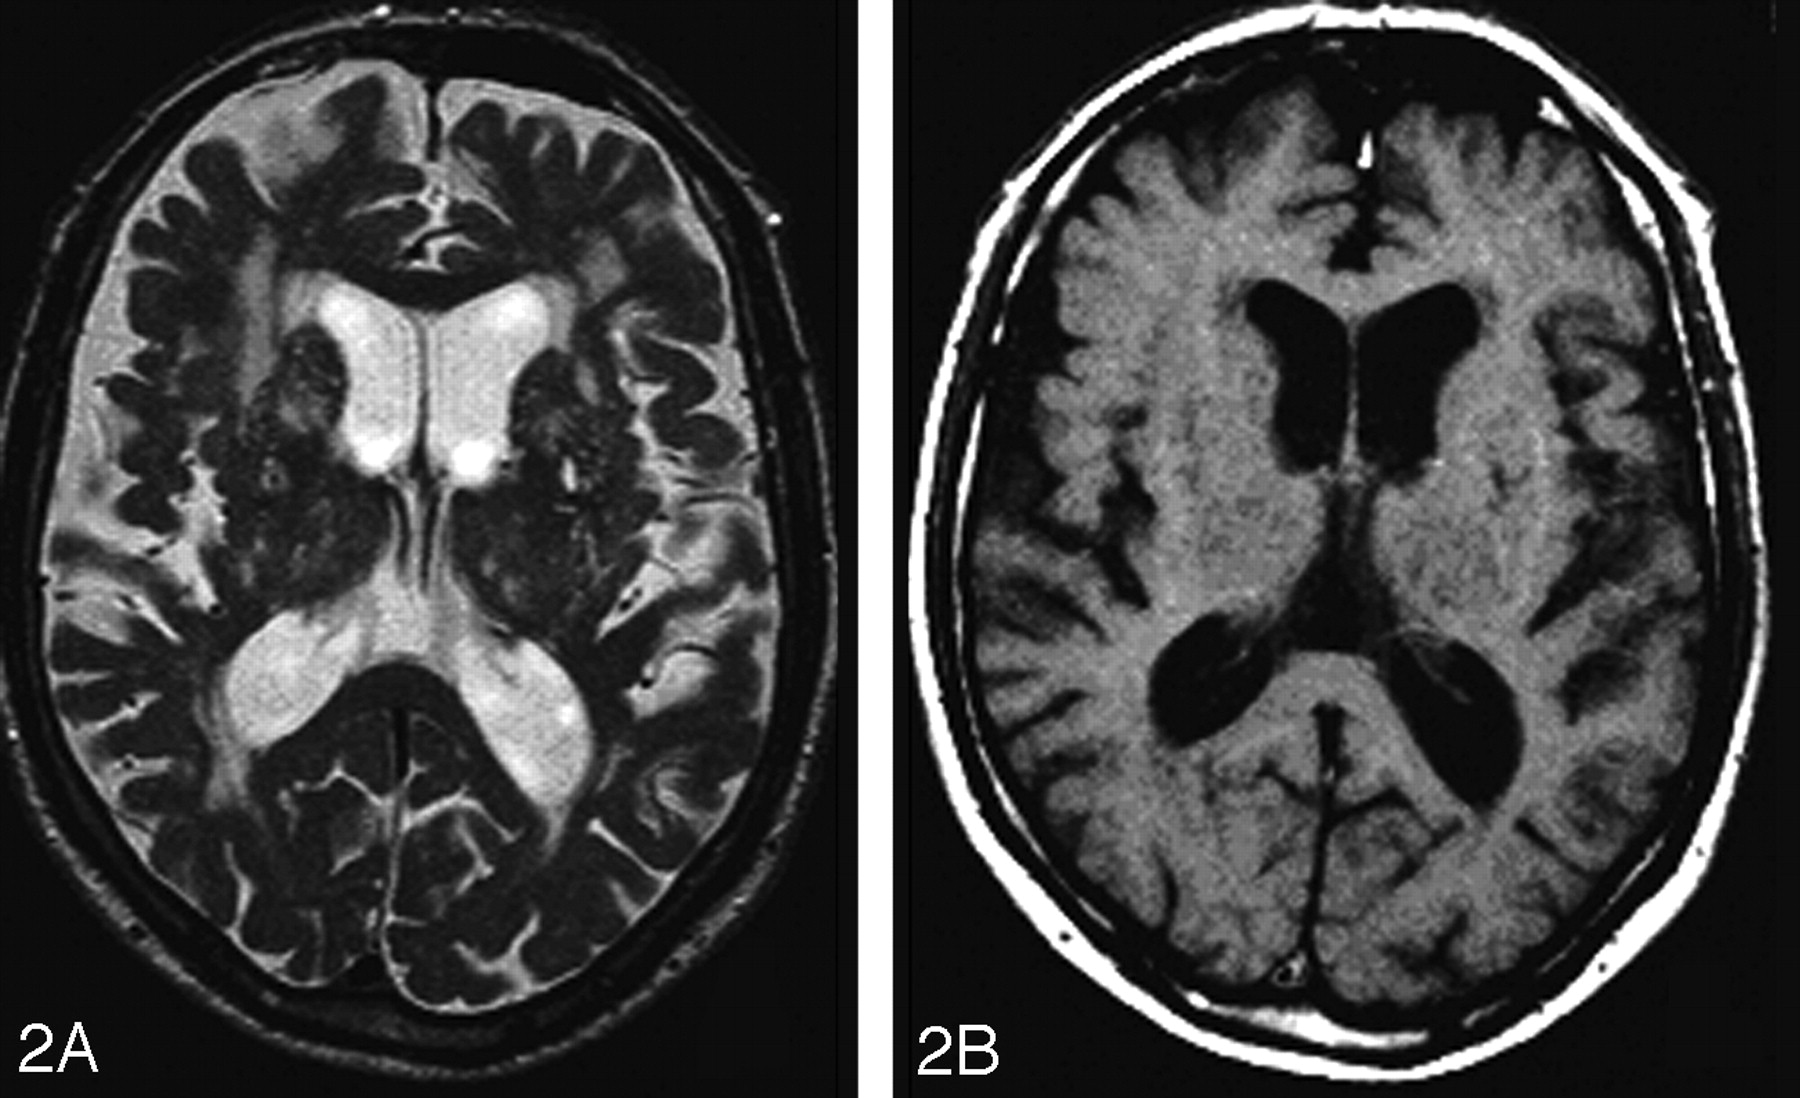

A second explanation for the observed differences in MTR between DWMH and PVWMH is not based on differences in vascularization between these brain areas but on differences in interstitial fluid dynamics. Because the brain is devoid of a lymphatic system, interstitial fluid is transported through the extracellular space of the brain and through the ependymal lining to the ventricles.22,23 Once the CSF is in the ventricles, the ependymal lining prevents the it from leaking into brain parenchyma. Because in elderly subjects with PVWMH, partial disappearance of the ependymal lining of the ventricles has been observed, it is conceivable that increased interstitial water resulting from ependymal discontinuation contributes to the high signal intensity on T2-weighted MR images.10 The similarity between the distribution of age-related PVWMH and the reversible periventricular high signal intensity on T2-weighted images that can be observed in patients with obstructive hydrocephalus (Fig 5) supports this hypothesis. The observed lower MTR values in PVWMH compared with DWMH could thus be based on the additional contribution of increased interstitial fluid concentration on MTR values in the periventricular white matter, which is absent in the deep white matter.

Subject (8-year-old) with an obstructive hydrocephalus secondary to infratentorial mass before (A, T1-weighted image; C, T2-weighted image) and after placement of a ventriculoperitoneal shunt (B, T1-weighted image; D, T2-weighted image). Notice the location and lining of the areas with increased signal intensity hypointensities on T1-weighted images in the periventricular white matter before drainage (A), disappearing after drainage (B).